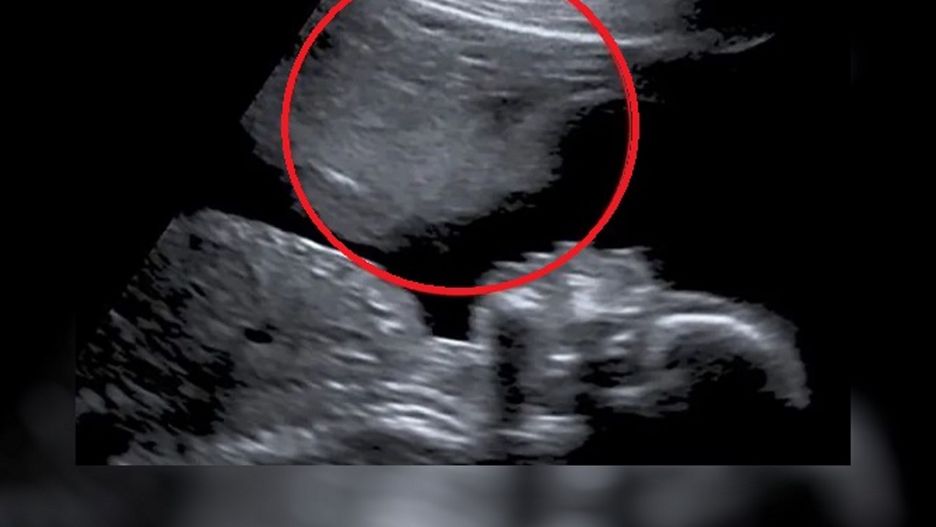

Jednak badanie w 20. tygodniu przysporzyło Stacey najwięcej wspomnień. Na monitorze ultrasonografu, tuż nad twarzą jej dziecka, pojawiła się druga, fantomowa postać. Według Stacey, to był "anioł stróż", który stanowił osłonę dla jej syna zapobiegając jakimkolwiek komplikacjom.

"Mam przeczucie, że istnieje coś (lub ktoś), kto tym razem dba o nas" - wyznaje. - "Mimo iż nie przestałam się martwić, poczułam ulgę."